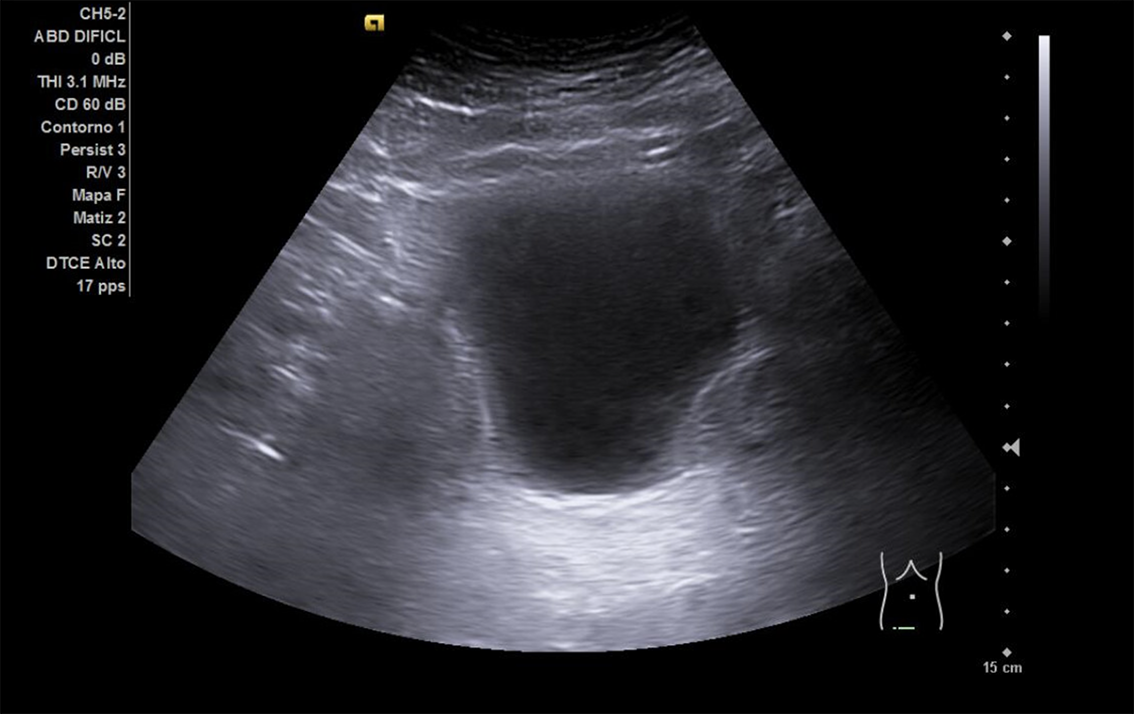

Descripción de los hallazgos ecográficos y las imágenes más relevantes para la resolución del caso

Se realiza ECO POCUS en la que se aprecia riñón derecho de morfología y tamaño normal. Riñón izquierdo con hidronefrosis grado III. A nivel de vejiga, bien replecionada se aprecia masa a nivel de pared izquierda adyacente a unión ureterovesical de 1.8 x 2,7 cm Ausencia de jet izquierdo.